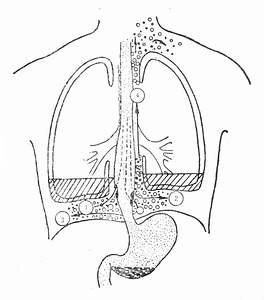

图37-2 自发性食管破裂部位

(2)体格检查多表现为急腹症,可有液气胸的相应体征,上腹压痛,肌紧张,甚至板状。食管、胃内容物进入胸、腹膜腔可引起化学性胸、腹膜炎,可以有急性化脓性纵隔炎及胸、腹膜炎的表现(图37-2)。